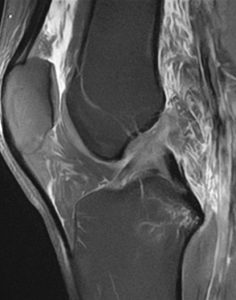

Polven magneettikuva sivulta

Sivusuuntainen (sagittaali) kuva polvesta.